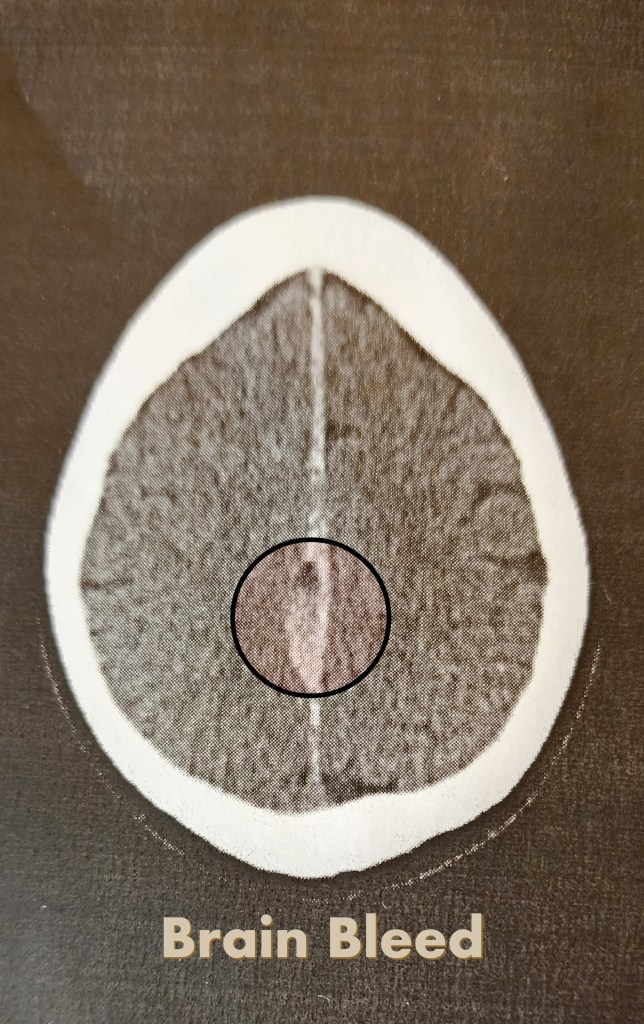

After the fall, I was diagnosed with a severe concussion accompanied by brain bleeding. Because of the seriousness of the injury, I was admitted to the hospital for observation. After being released, I was sent home with very strict medical instructions designed to give my brain the best possible chance to heal fully.